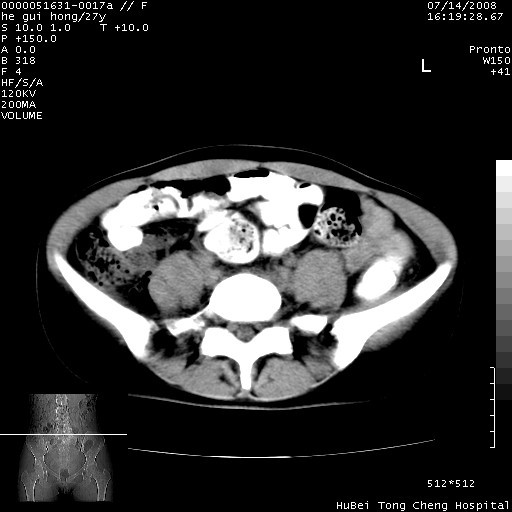

以下是引用杀毒软件在2008-7-20 8:03:00的发言:[br]支持双侧卵巢囊腺瘤可能性大!

以下是引用zjzjr在2008-7-20 13:36:00的发言:[br]双侧附件囊腺瘤可能性大!